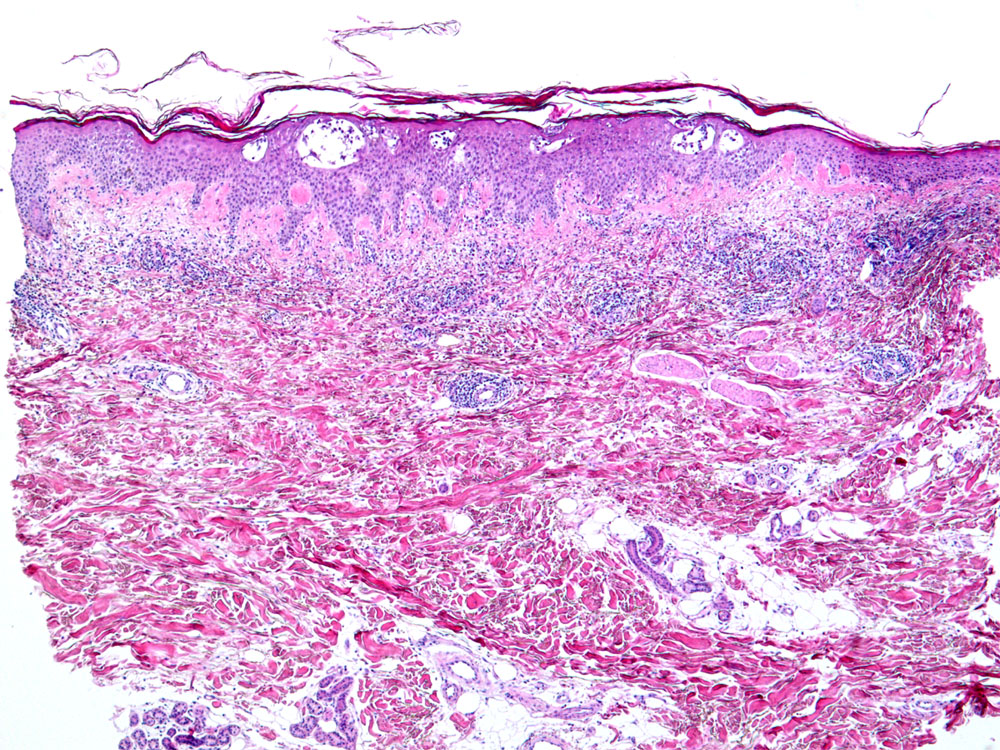

Mikroskopische Befunde:

Histologisch zeigen akute Ekzeme eine ausgeprägte Spongiose mit intraepithelialer Bläschenbildung, eine Parakeratose und Krustenauflagerungen, im chronischen Stadium eine Verminderung der Spongiose, eine Akanthose und Hyperparakeratose. Bei alten Läsionen können Parakeratosehügel und eine Epidermishyperplasie der einzige Hinweis auf eine spongiotische Dermatitis sein. Die Epidermishyperplasie ist teilweise eine Folge des chronischen Reibens und Kratzens der juckenden Haut. Das Entzündungsinfiltrat in der oberen Dermis besteht aus Lymphozyten und Histiozyten, zum Teil auch aus neutrophilen und eosinophilen Granulozyten. In der Epidermis dominieren Lymphozyten (lymphozytäre Exozytose). Akute, subakute und chronische Veränderungen können beim gleichen Patienten nebeneinander vorkommen.

Morphologische Merkmale:

• Verdickte Epidermis (Akanthose)

• Spongiose (interzelluläres Ödem der Epidermis)

• Spongiotische Vesikel (intraepitheliale Bläschenbildung)

• Parakeratotische Verhornung (Verhornte Zellen mit erkennbaren Zellkernen)

• Ödem der papillären Dermis (Aufhellung)

• Oberflächlich dermales perivaskulär betontes Entzündungsinfiltrat

• Lymphozyten, Histiozyten, neutrophile und eosinophile Granulozyten